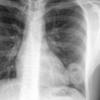

Case 18 Cavitating pneum/Abscess PA

Date: 07/09/2006

Views: 5006